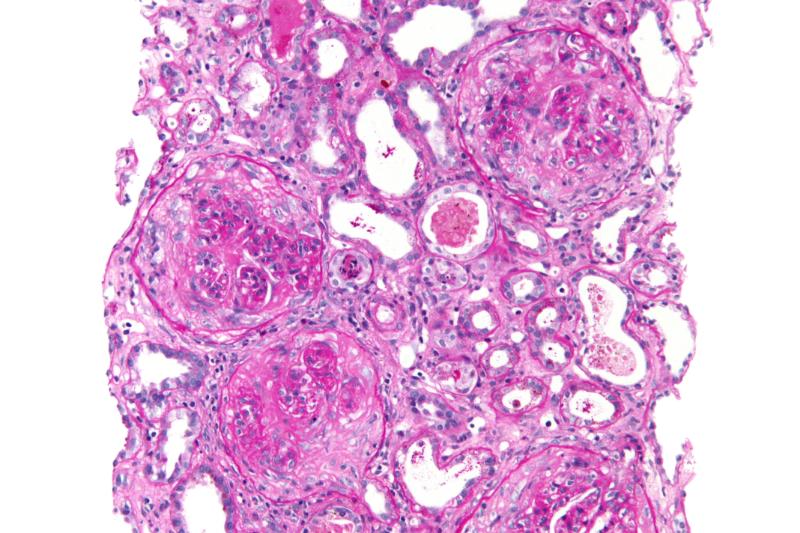

- Пневмониты гиперчувствительности (экзогенные аллергические альвеолиты): Это воспаление альвеол и мелких бронхиол в ответ на вдыхание органической пыли (плесень, белки птиц, химикаты). В отличие от астмы, где поражаются крупные бронхи, при пневмоните гиперчувствительности преобладает интерстициальное поражение, что проявляется рестриктивными нарушениями на спирометрии и характерными изменениями на КТ лёгких (матовое стекло, центрилобулярные узелки).